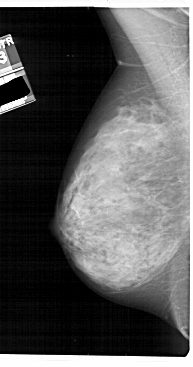

A_1912_1.LEFT_CC

LEFT_CC LINES 5086 PIXELS_PER_LINE 2836 BITS_PER_PIXEL 12 RESOLUTION 43.5 NON_OVERLAY